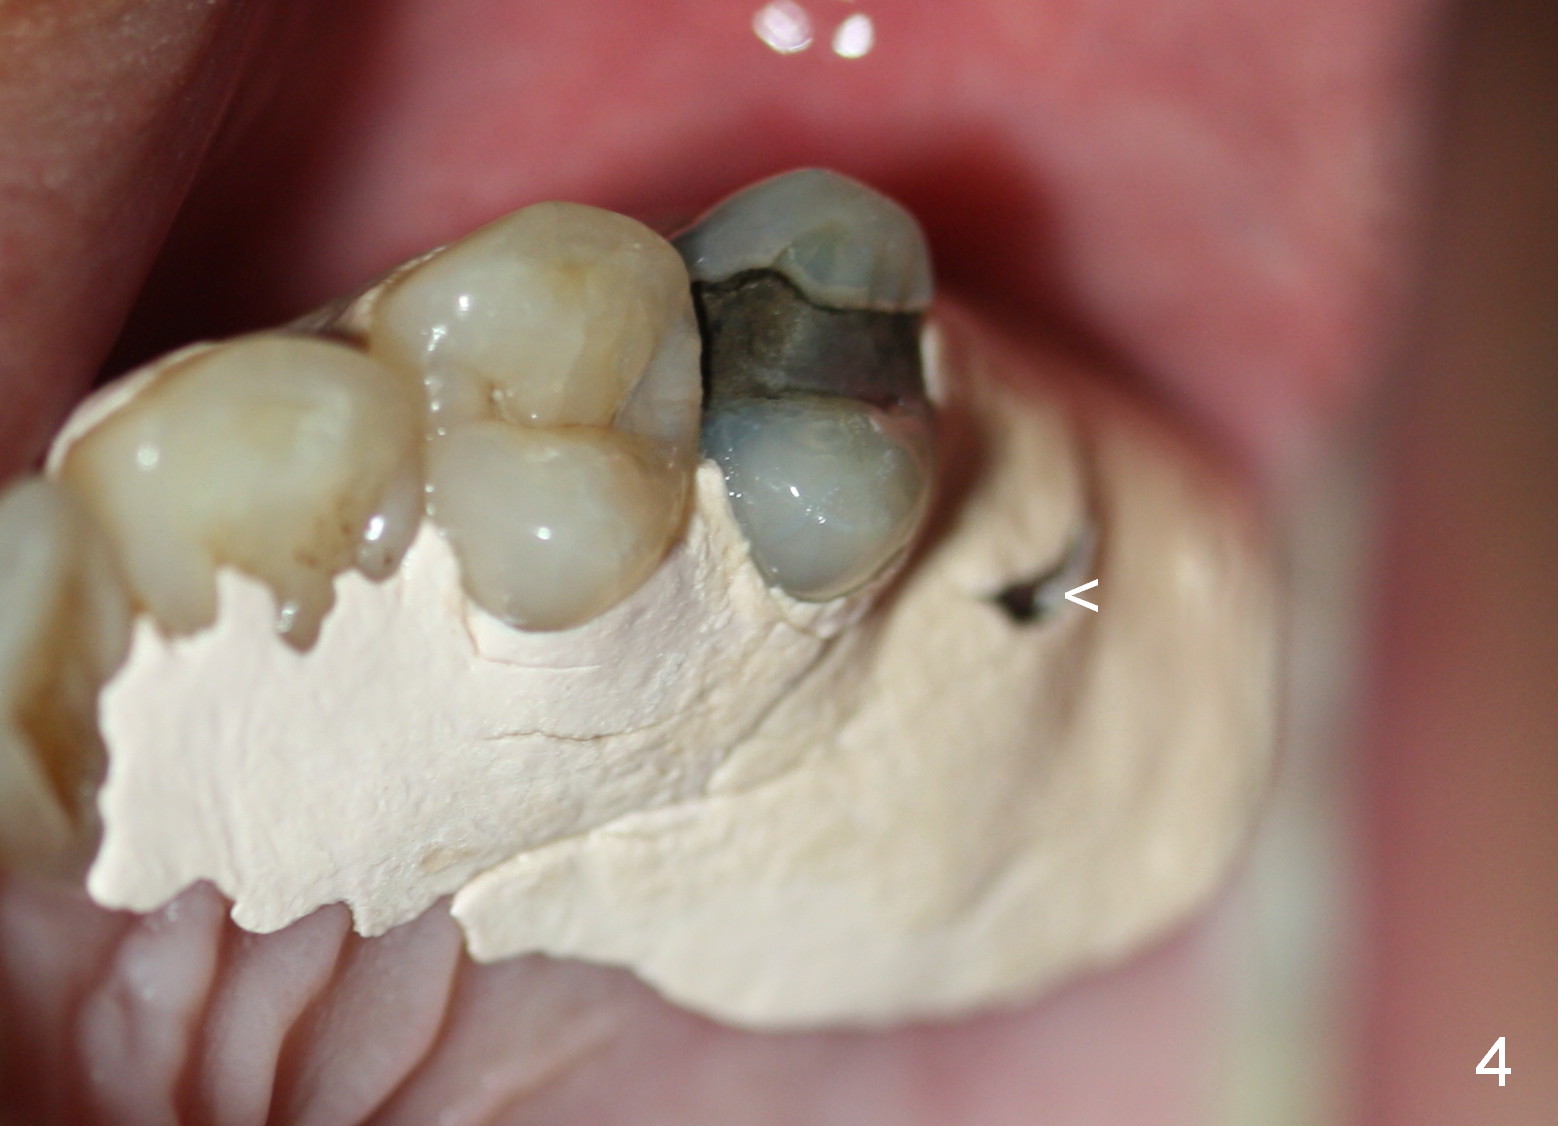

The implant recipient site is wide buccopalatally. After incision, a 3.9/4.7 mm trephine bur (from UF Extra Wide Implant kit) is used to initiate osteotomy 2.5 mm from the distal surface of the tooth #13. The depth of the trephine bur is 2 mm. The block of bone is difficult to be removed from the osteotomy. It is pushed into the sinus with a 3.5 mm osteotome with minor membrane perforation. The perforation is getting worse when allograft and Osteogen is being pushed upward. It is repaired with insertion of Osteotape and more durable collagen membrane, followed by bone graft. The osteotomy opening is enlarged slightly with a 6x6 mm tapered drill, followed by insertion of a 6.5 mm tap. When a 7x6 mm bone-level implant is placed with >60 Ncm, the axis is not parallel to that of the neighboring teeth. The implant is backed up and re-directed. The trajectory is changed within normal limit (Fig.2); the torque is slightly less than before. The distal 2nd thread is outside the crestal bone (Fig.2 <). The implant is placed deeper so that the distal 2nd thread is almost subcrestal (Fig.3). The remaining threads are covered by bone graft, followed by collagen membrane. There is tension to close the wound. A cemented abutment is placed (6.8x4(2) mm) to hold perio dressing in place. Postop instruction is given, including sinus precaution. Afrin is prescribed. The patient continues using Amoxicillin and Chlorhexidine postop. Surprisingly, there is no sinus symptom postop. The perio dressing remains in place 1 week postop (Fig.4). Later on, mild infection develops around the implant orally. One week of Amoxicillin is prescribed. The symptom improves. One month postop, the patient returns for follow up: the distal implant plateau is exposed (Fig.5 I). A provisional is fabricated for protection of the wound and comfort (Fig.6 P). The exposed plateau should be able to be covered by the gingiva in a few months.